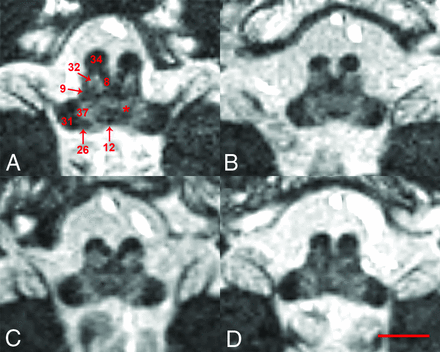

Superior-to-inferior axial in vivo MR images parallel to the intercommissural plane for the brain stem (number denotes the position below the plane), including the superior midbrain (A, 8.8 mm), inferior midbrain (B, 15.2 mm), midbrain-pons junction (C, 18.4 mm), superior midpons (D, 25.5 mm), inferior midpons (E, 29.5 mm), inferior pons (F, 35.9 mm), superior or “open” medulla (G, 43.1 mm), closed medulla at the sensory decussation (H, 47.1 mm) and motor decussation (I, 55.1 mm). A 26-year-old healthy control female subject, 0.8-mm isotropic resolution, 9 individual datasets coregistered and averaged, 2 imaging sessions with ∼2-hour 15-minute total scan time (scale bar = 5 mm). Please see the Table and Results section for explanation of labeled structures.

Labeling in the figures emphasizes unambiguous structures that can be identified well on the images. Most of these labeled structures are well-known to clinicians familiar with brain stem anatomy (eg, the medial longitudinal fasciculus). Directly labeled visible structures also can be used to generate more exact indirect localization for other bordering internal brain stem structures. Figure 4 provides a highly detailed example of this approach for the inferior midbrain where the likely positions of multiple additional structures can be estimated relative to the borders and anatomic spaces formed between the medial longitudinal fasciculus, medial lemniscus, and decussation of the superior cerebellar peduncles. Annotation at this level of detail with descriptions of functional relevance is possible throughout the brain stem, but is beyond the scope of this initial report. Other selected examples of indirect localization that may be of general interest include the oculomotor complex (bright region posteromedial to the central tegmental tract in Fig 1A), pedunculopontine nucleus (bright region medial to the medial lemniscus and lateral to the decussation of the superior cerebellar peduncles, in Fig 1B), locus coeruleus (bright region posterior to the central tegmental tract and medial to the superior cerebellar peduncle in Fig 1C), and facial nucleus (bright region posterolateral to the central tegmental tract and medial to the cerebellar peduncles in Fig 1F). An inferior notch along the medial aspect of the left middle cerebellar peduncle with gray matter signal intensity in Fig 2D is the cochlear nucleus.

Direct, unambiguous identification of many myelinated structures in the inferior midbrain (A) also helps improve the spatial accuracy for indirect localization of bordering brain stem nuclei and pathways that are less densely myelinated at this level (B). The ventral trigeminothalamic tract61 is located between the decussation of the superior cerebellar peduncles and medial lemniscus. Subtle dark bumps on the anterior and posterior aspects of the decussation15 are consistent with the rubrospinal17 and tectospinal tracts,58 respectively. The bright midline structure anterolateral to the medial longitudinal fasciculus8 should be the substantia nigra pars compacta.5 The reticular formation60 is the bright region posterolateral to the medial longitudinal fasciculus and central tegmental tract,10 and anterolateral to the periaqueductal gray.11 This region will also contain the locus coeruleus. The trochlear nucleus59 should be along the posterior border of the medial longitudinal fasciculus. The interpeduncular nucleus57 is off-midline anterior to the decussation of the superior cerebellar peduncles. Similar indirect localization can be derived at other brain stem levels, but is beyond the scope of this initial report.